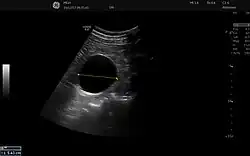

Sistema digestivo

En la ecografía abdominal, se forman imágenes de los órganos sólidos del abdomen como el páncreas, la aorta, la vena cava inferior, el hígado, la vesícula biliar, los conductos biliares, los riñones y el bazo. Las ondas sonoras son bloqueadas por el gas en el intestino y atenuadas en diferentes grados de grasa, por lo que hay capacidades de diagnóstico limitadas en esta área. El apéndice a veces se puede ver cuando se inflama.[20]